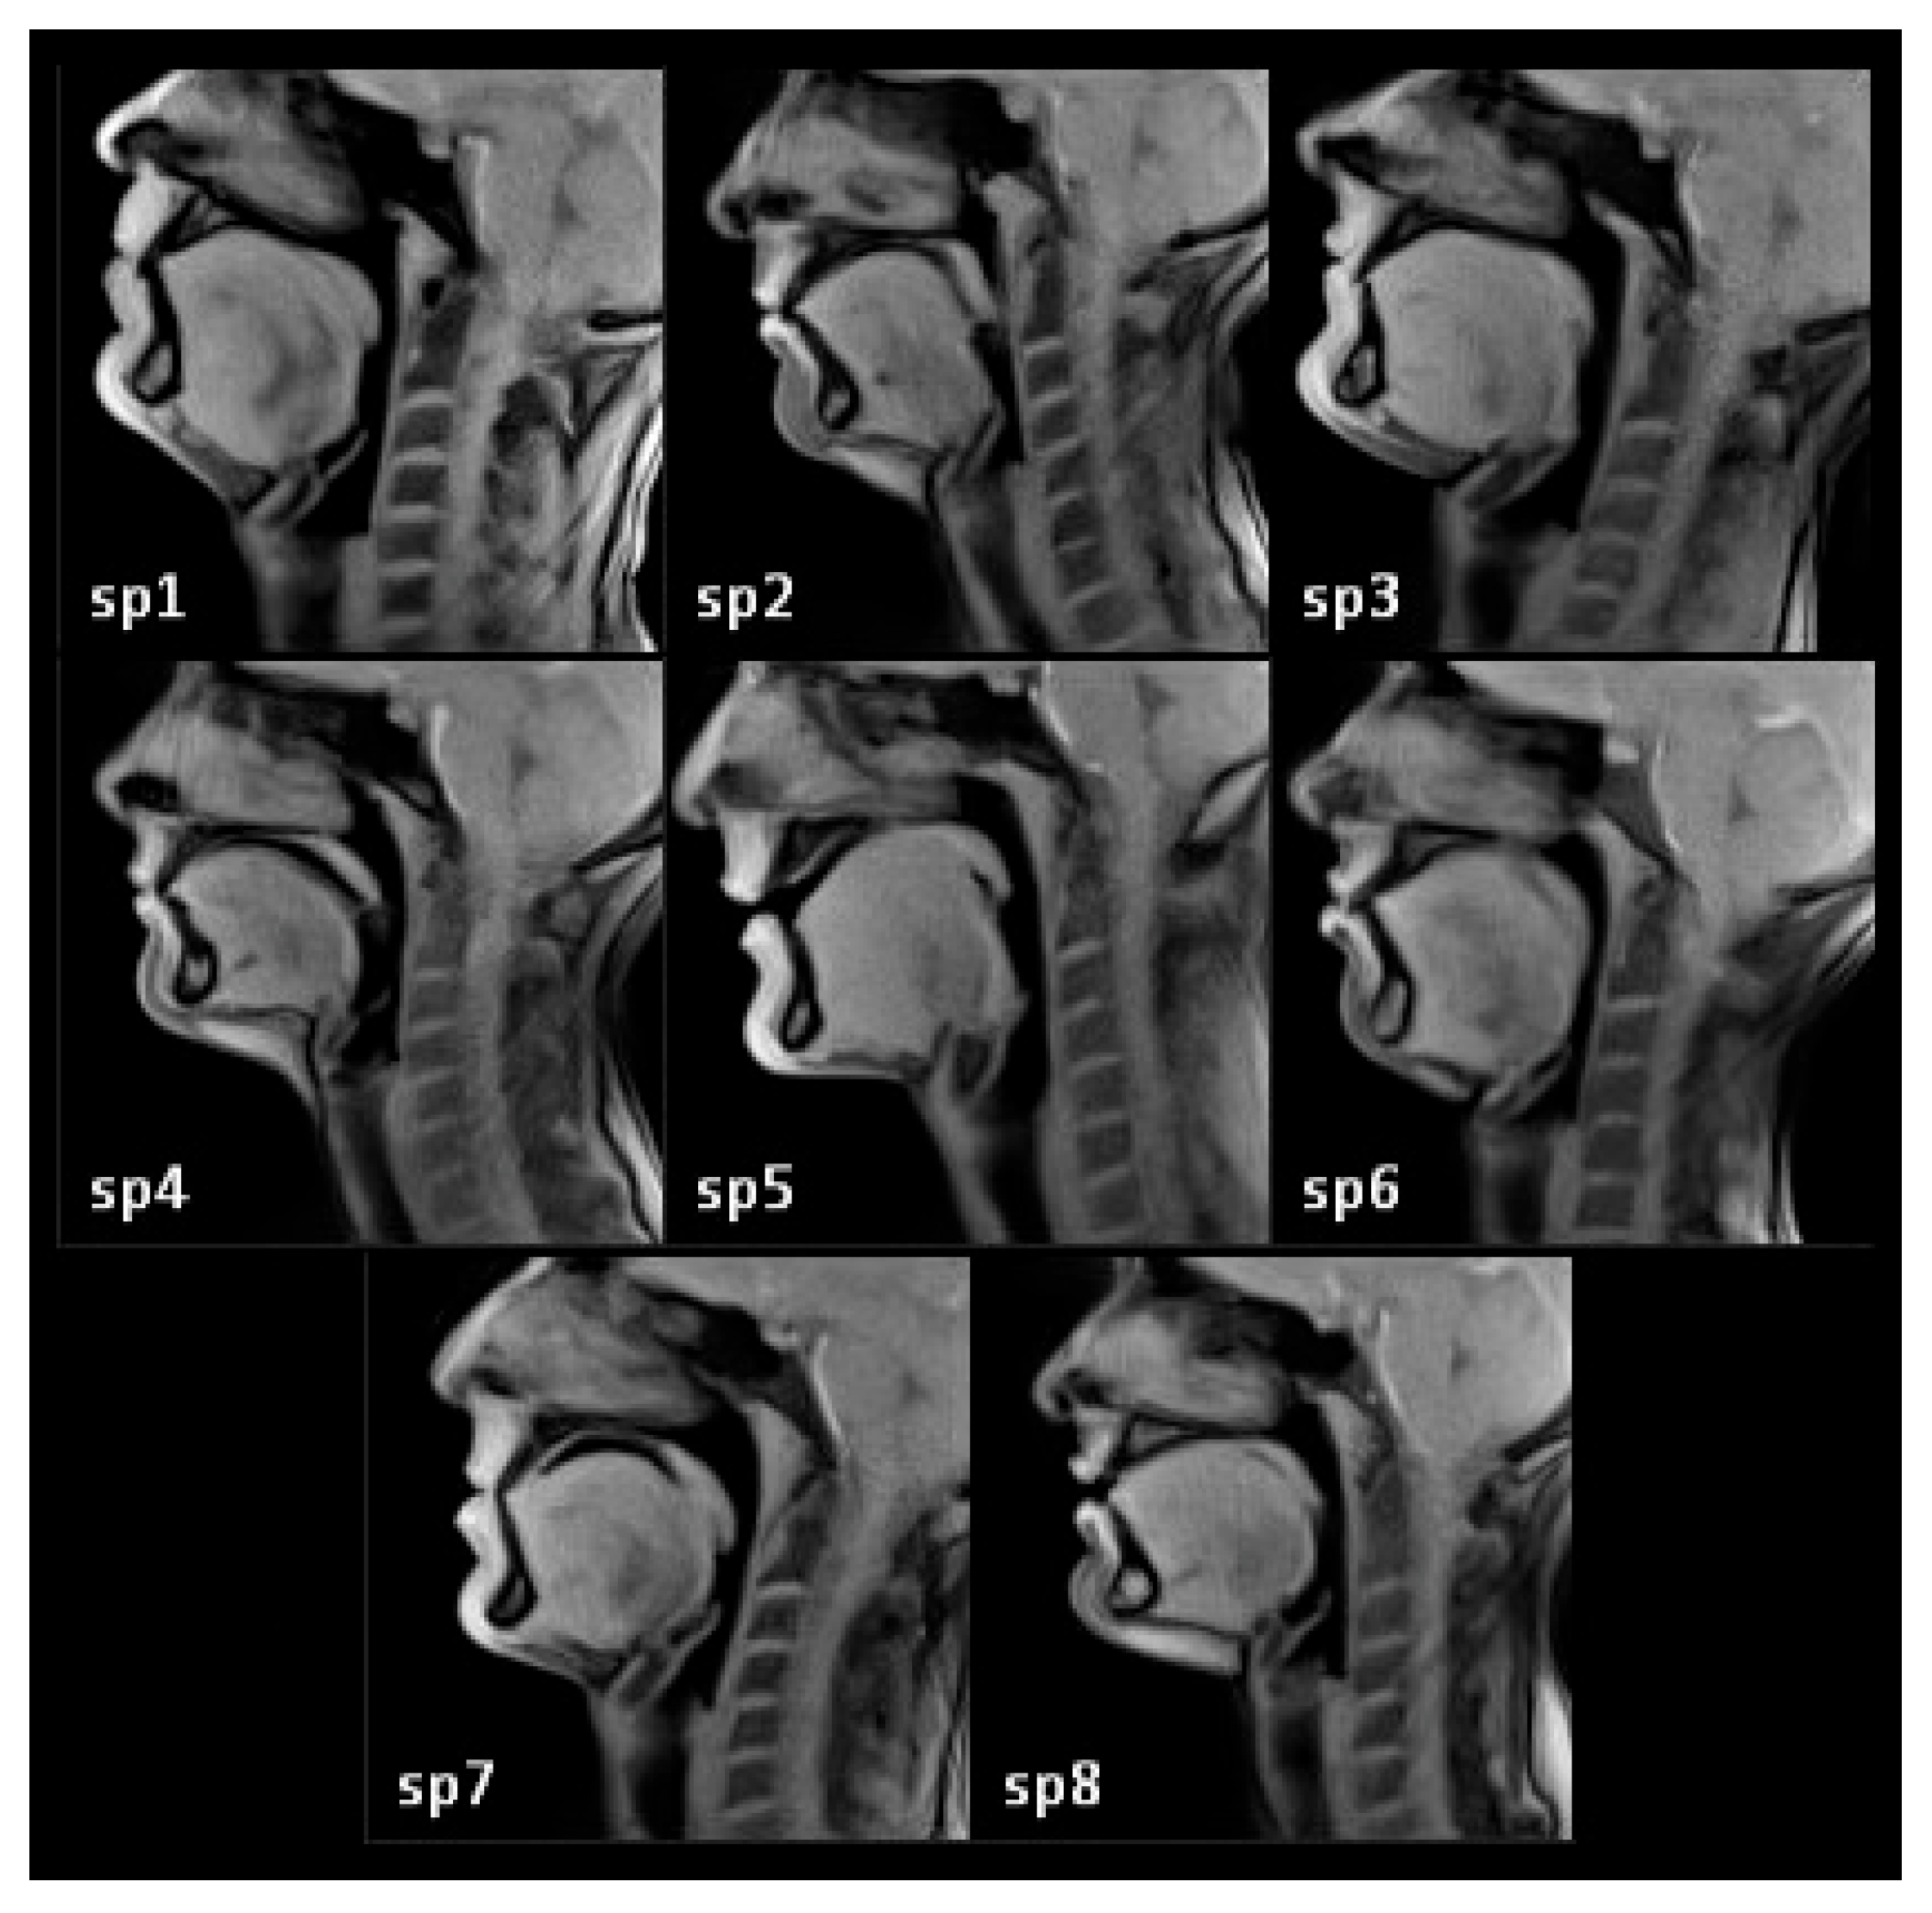

2.1. Subjects